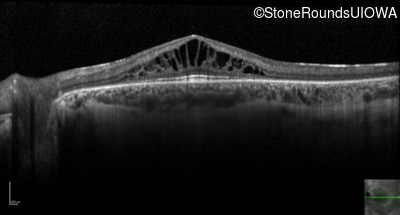

Optical Coherence Tomography - Right - 20/32 -2

Exemplar / OCT Stack

OCT Stack